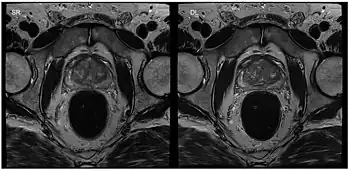

(a,c) CINE and (b,d) RT CMR at 1.5 T of a patient with atrial fibrillation in a mid-ventricular SA view during end-diastole (a,b) and end-systole (c,d). CINE mages have reduced diagnostic quality (score 1), while RT images present with good diagnostic quality.

Cardiac MRI

Although applications of real-time MRI cover a broad spectrum ranging from non-medical studies of turbulent flow[26] to the noninvasive monitoring of interventional (surgical) procedures, the most important application making use of the new capabilities is cardiovascular imaging.[1] Previous cardiac MR (CMR) used cine techniques to capture the periodic motion of the heart. However, this is not feasible for patients with arrhythmia, where the cardiac cycle is unpredictable.[27] With the new method it is possible to obtain movies of the beating heart in real time with up to 50 frames per second during free breathing and without the need for a synchronization to the electrocardiogram.[28] A study performed by Laubrock et al.[27] demonstrated that RT-MRI produced higher quality images with a higher SNR than cine CMR with a bSSFP sequence and radial k-space sampling. RT-MRI also removes the need for breath-holding while imaging, leading to a more comfortable experience for the patient as well.[27]